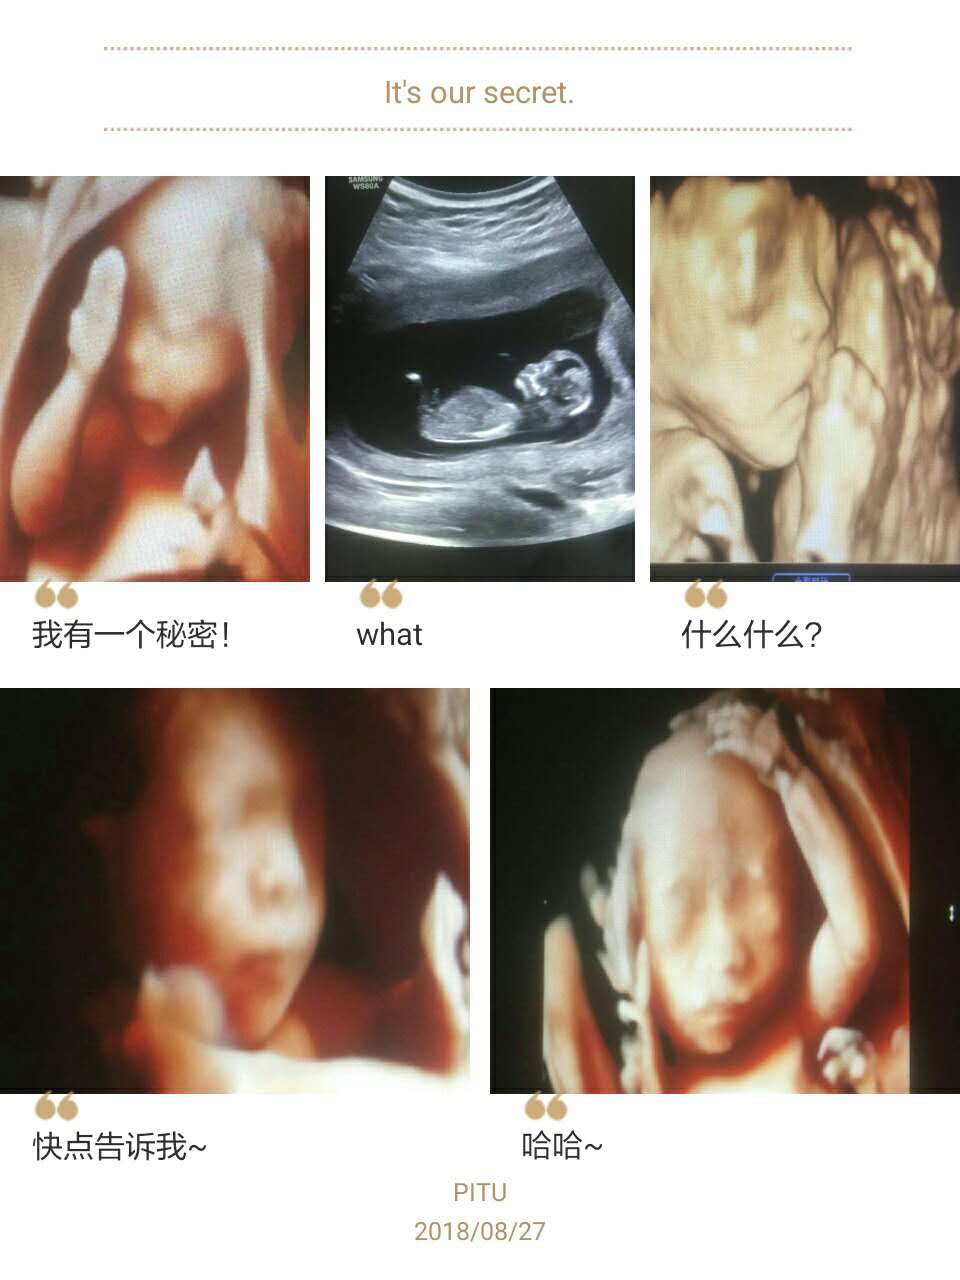

安陽(yáng)市第二人民醫院超聲科新進(jìn)高端四維彩超,圖像高清,功能齊全,每天迎接著(zhù)每位準媽媽的到來(lái),四維彩超不僅可以對胎兒的生長(cháng)情況做個(gè)全面細致的檢查,盡早發(fā)現胎兒發(fā)育異常,還能給宮內寶寶拍出漂亮可愛(ài)的照片?,F整理了一些四維照片送給大家,希望你們能喜歡,歡迎來(lái)約哦!